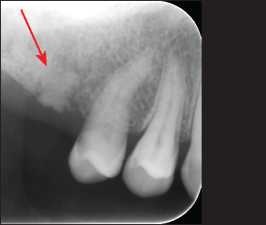

All retained roots or root fractures that are close to the tissue surface or exhibit pathological signs should be removed (Figure 10-2).